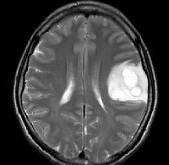

问题 女,33岁,三个月前有右上肢及右颜面部麻木,伴耳鸣及头昏,请根据所提供图像,选择最可能的诊断()

选项 A.脑脓肿 B.星形细胞瘤 C.脑结核 D.脑转移瘤 E.脑血吸虫病

答案 B